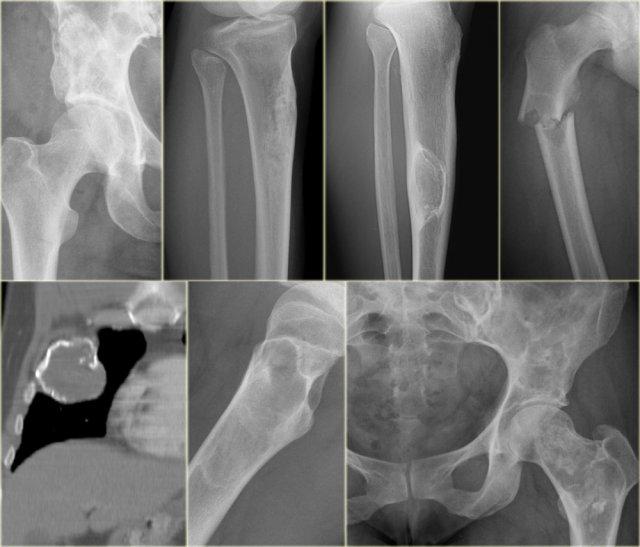

Bên trái là các u xương và tổn thương dạng u xương lành tính được xác định rõ ràng phổ biến nhất.

Các tổn thương này đôi khi được gọi là tổn thương nang lành tính, đây là một thuật ngữ không chính xác vì hầu hết chúng không phải dạng nang, ngoại trừ SBC và ABC.

Đúng là ở bệnh nhân dưới 30 tuổi, ranh giới được xác định rõ ràng có nghĩa là chúng ta đang xử lý một tổn thương lành tính, nhưng ở bệnh nhân trên 40 tuổi, di căn và đa u tủy xương cần được đưa vào chẩn đoán phân biệt.

Bên trái là bảng liệt kê các khối u xương tiêu xương được xác định rõ ràng và các tổn thương giả u theo các nhóm tuổi khác nhau.

Notice the following:

-

Ở bệnh nhân

Ở bệnh nhân > 40 tuổi, di căn xương và đa u tủy xương là những khối u xương tiêu xương được xác định rõ ràng phổ biến nhất. - Bệnh nhân có u nâu trong cường cận giáp nên có các dấu hiệu khác của cường cận giáp hoặc đang chạy thận nhân tạo.

- Sự phân biệt giữa u sụn lành tính và sarcoma sụn độ thấp có thể không thể thực hiện được chỉ dựa trên các kết quả hình ảnh học.

- Infection is seen in all ages.